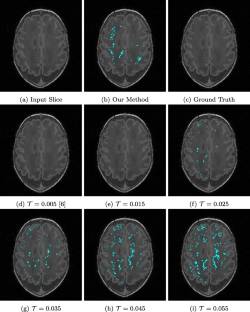

White matter injury (WMI) is the most prevalent brain injury in the preterm neonate leading to developmental deficits. However, detecting WMI in magnetic resonance (MR) images of preterm neonate brains using traditional WM segmentation-based methods is difficult mainly due to lack of reliable preterm neonate brain atlases to guide segmentation. Hence, we propose a segmentation-free, fast, unsupervised, atlas-free WMI detection method. We detect the ventricles as blobs using a fast linear maximally stable extremal regions algorithm. A reference contour equidistant from the blobs and the brain-background boundary is used to identify tissue adjacent to the blobs. Assuming normal distribution of the gray-value intensity of this tissue, the outlier intensities in the entire brain region are identified as potential WMI candidates. Thereafter, false positives are discriminated using appropriate heuristics. Experiments using an expert-annotated dataset show that the proposed method runs 20 times faster than our earlier work which relied on time-consuming segmentation of the WM region, without compromising WMI detection accuracy.

Fig. 4